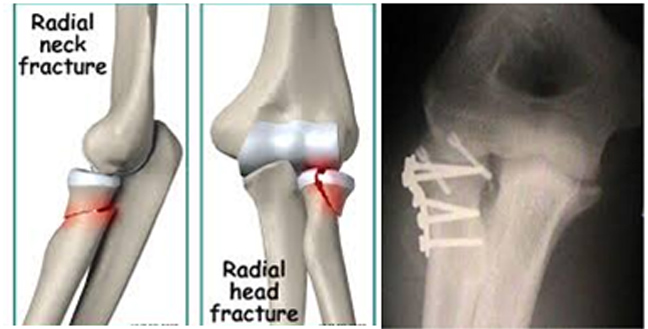

Τα κατάγματα στην περιοχή του αγκώνα είναι συχνά και αφορούν και τα τρία οστά που σχηματίζουν τον αγκώνα, δηλαδή το κάτω μέρος του βραχιονίου, το άνω μέρος της κερκίδας και το άνω μέρος της ωλένης.

Το κάτω άκρο του βραχιονίου σχετίζεται με την δυνατότητα του αγκώνα να κάνει κάμψη και έκταση. Το άκρο της ωλένης, το ωλέκρανο σχετίζεται μόνο με την έκταση. Η κεφαλή της κερκίδος με τις στροφές (πρηνισμό-υπτιασμό) του αντιβραχίου.

Συνεπώς στα κατάγματα του αγκώνα, όταν έχει σπάσει η κεφαλή της κερκίδος δεν δύναται ο τραυματίας να κάνει στροφές (δεν δύναται ο τραυματίας να κάνει στροφές (πρηνισμός-υπτιασμός).

Όταν ο τραυματίας μπορεί να κάνει (σιγά-σιγά) κάμψη και έκταση του αγκώνα, αλλά πονάει και δυσκολεύεται να κάνει στροφές, δεν έχει κάταγμα του βραχιονίου, ούτε του ωλεκράνου, αλλά της κεφαλής της κερκίδος.

Χρειάζεται όμως ακτινογραφία, γιατί αν η κεφαλή έχει «σπάσει» σ΄ όλο το εύρος της, τότε χρειάζεται χειρουργική αποκατάσταση.